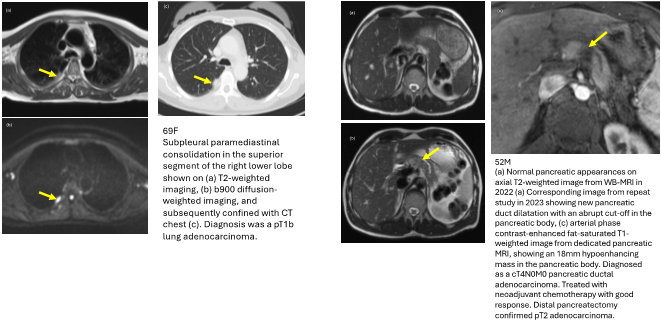

• The project has demonstrated that WB-MRI could detect early cancers in asymptomatic patients with Li Fraumeni syndrome.

• In the cohort, ten cancers were diagnosed with the help of WB-MRI. Seven cancers (70%) were early stages (TNM stage 0-2) and were treated with curative intent; three cancers (30%) were late stages (TNM stage 3-4).